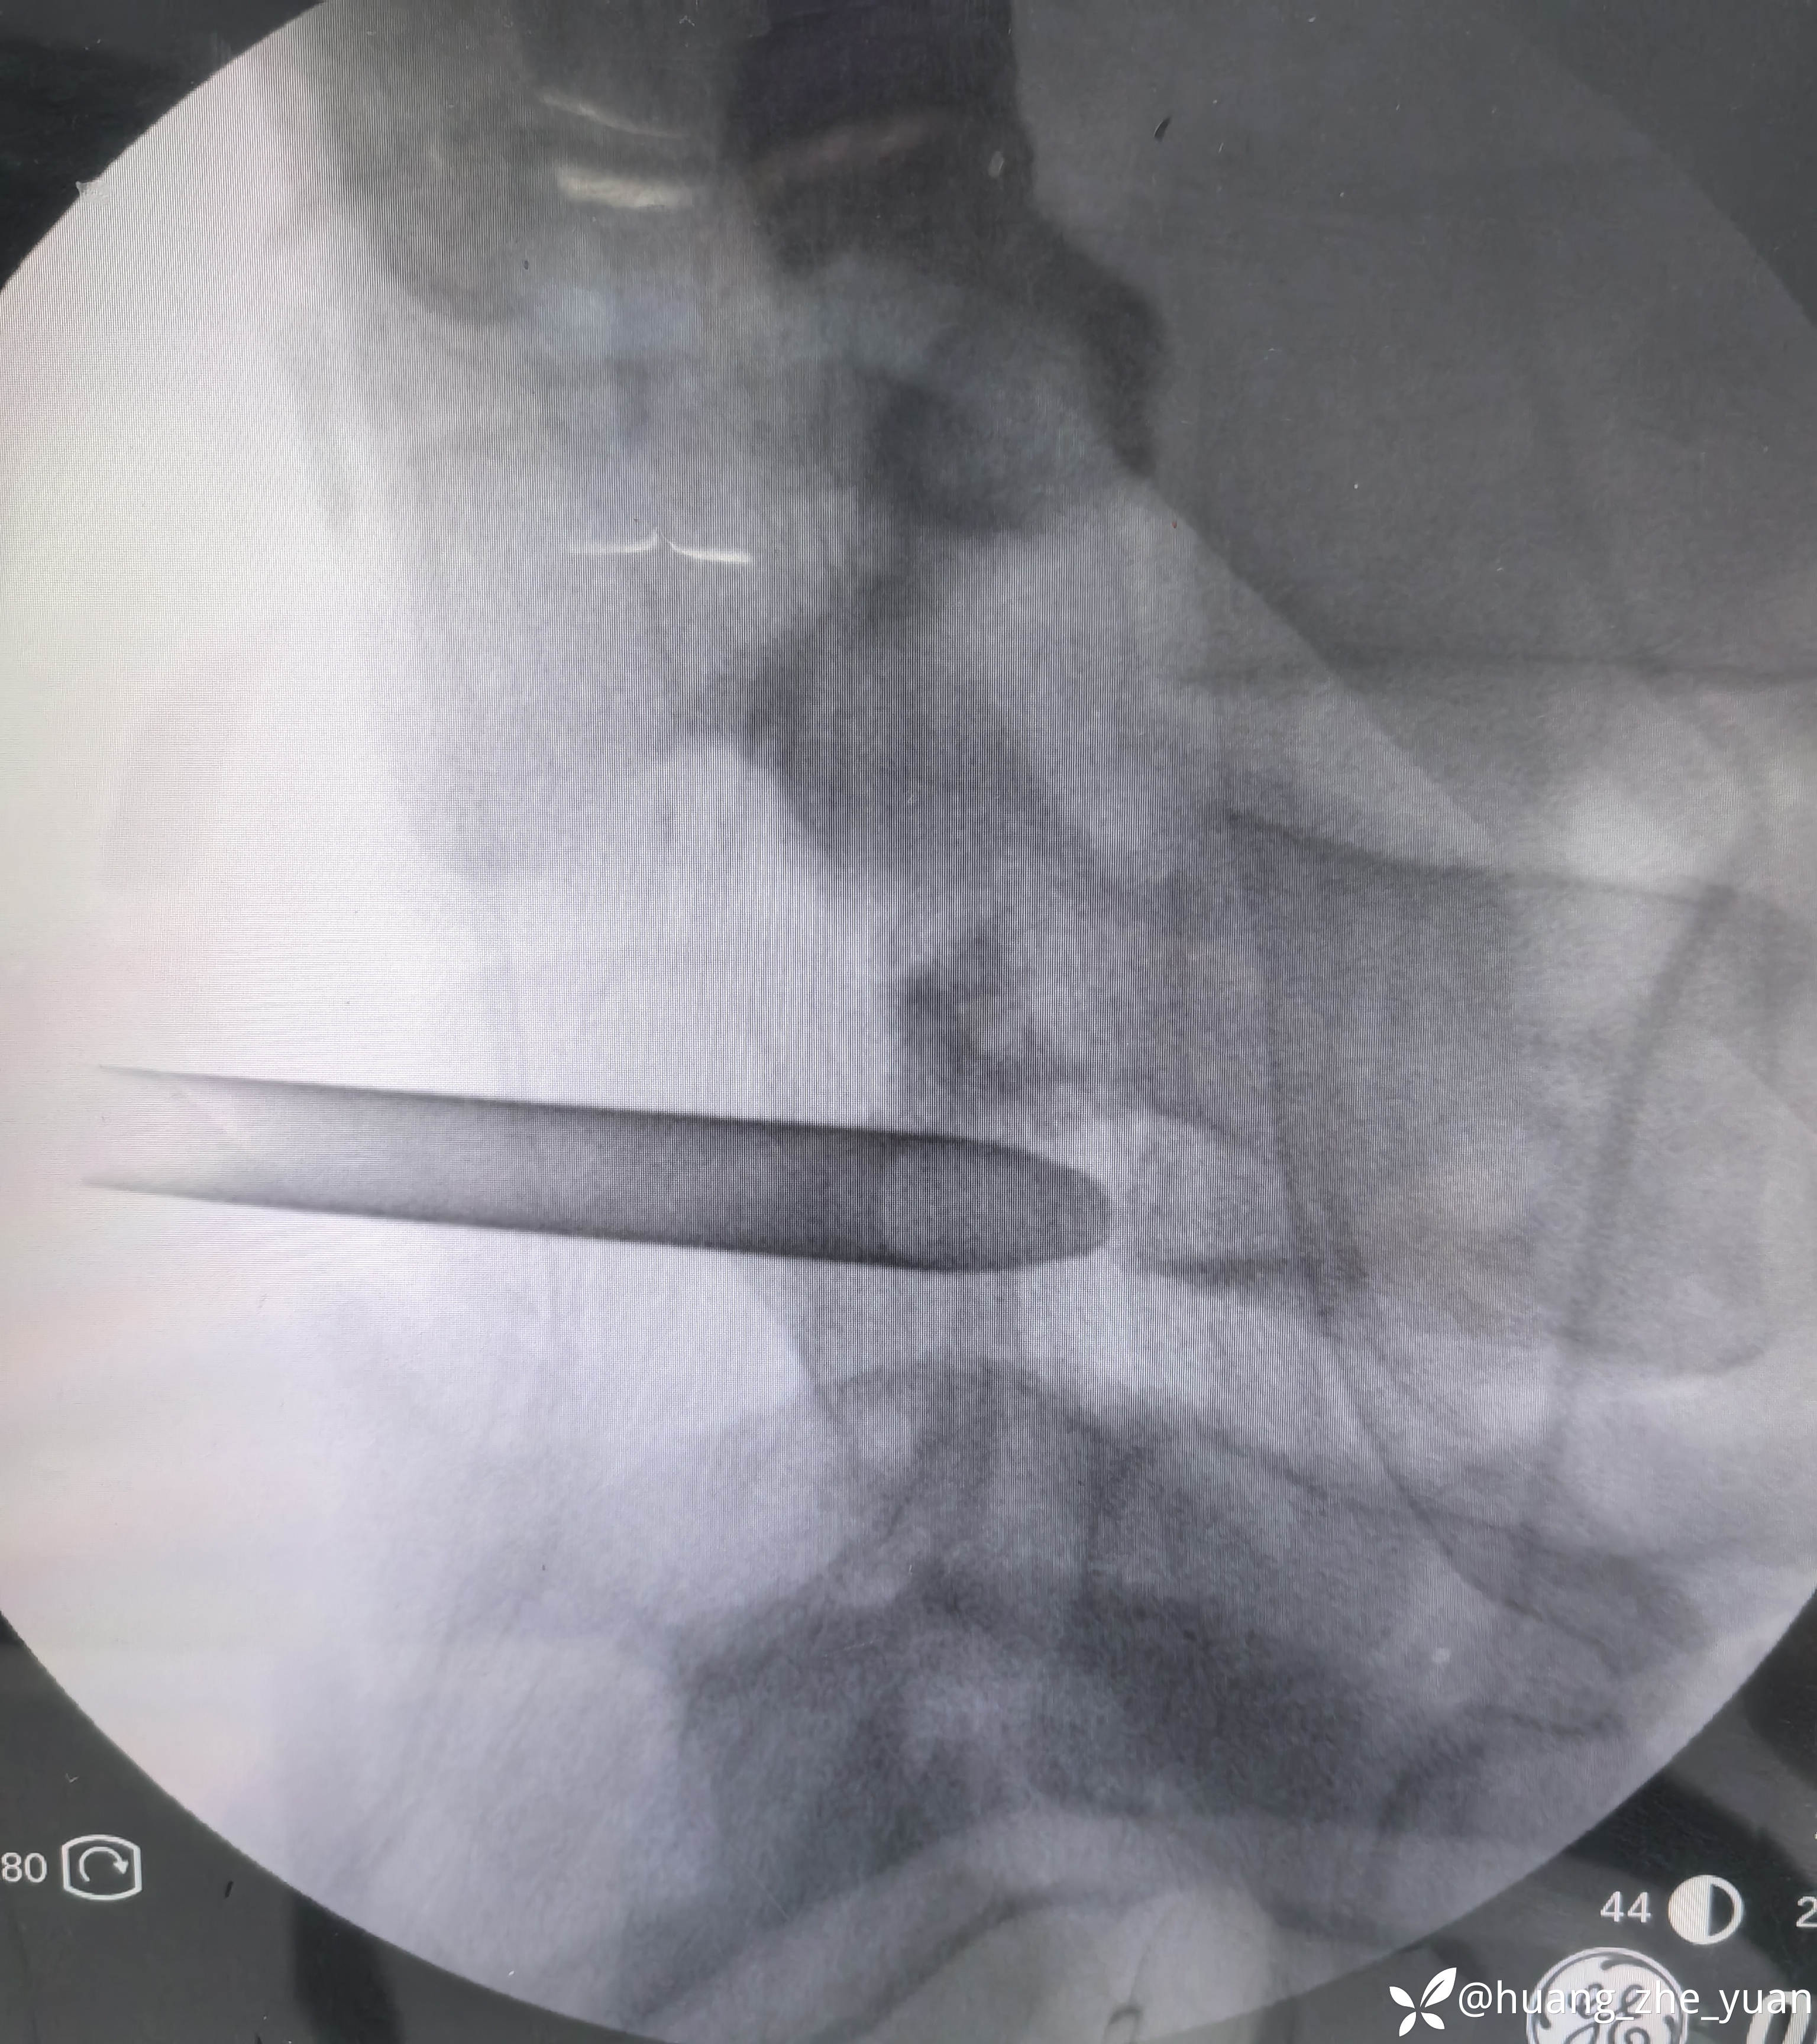

局麻单切口做两节。

椎间孔少量成形。椎间盘做微创消融。